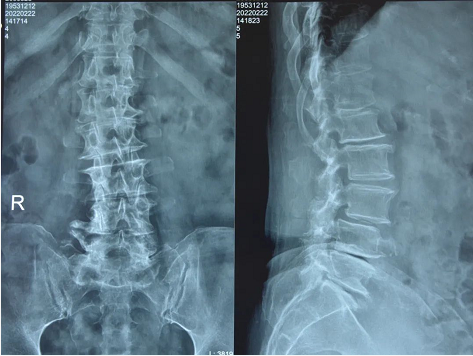

患者术前影像

然而,接诊的业务院长韦向荣仔细询问发病过程和查体后,发现病情另有玄机。经过磁共振辅助检查,患者不仅存在颈椎间盘突出和腰椎间盘突出的问题,但更严重的问题出现在胸椎,黄韧带钙化引起的胸椎管狭窄症。“像她这样累积多年的病症,尤其是胸椎、腰椎(T12-L1,L3-4,L4-5)多节段狭窄,在临床上并不是十分的多见。”韦向荣表示。